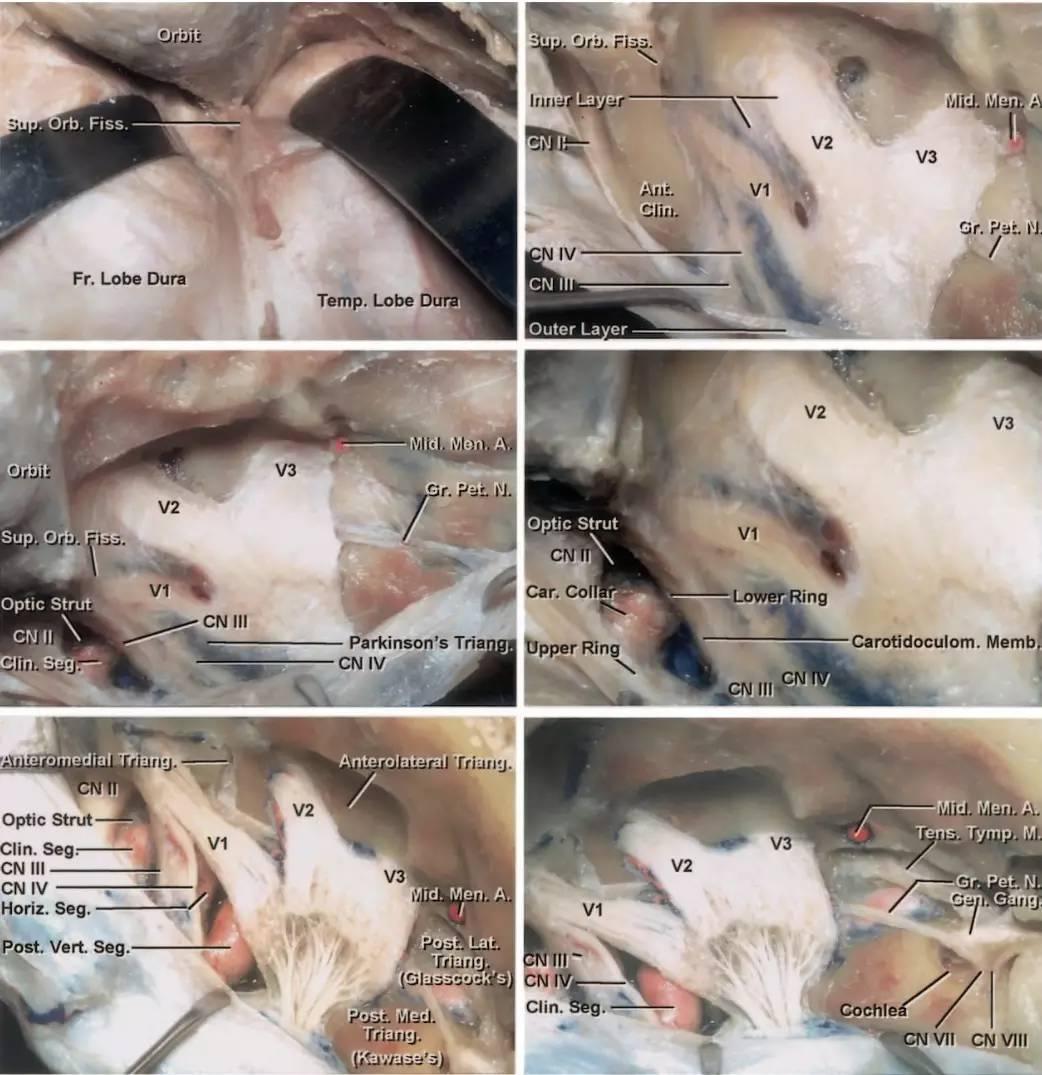

图3:硬膜外入路行右侧海绵窦的手术学解剖。颞前-眶颧开颅及硬膜外前床突切除术已完成,眶上裂的外侧缘已显露(左上图,此时硬膜外前床突切除术其实尚未完成,译者注)。在眶上裂的外侧缘处切断额颞或脑膜眶硬膜返折,将海绵窦外侧壁的外层从内层上剥离。因此,掀开海绵窦外侧壁的外层(脑膜层),即可显露融入外侧壁内层的颅神经(右上图)。

切断脑膜中动脉,继续向后内侧剥离硬膜,即可暴露岩浅大神经,其通常行于岩骨段颈内动脉上方,故可作为其定位标志。沿中颅窝剥离硬膜的内侧界为前岩床突硬膜返折,后界为岩骨嵴(左中图)。床突旁区域的放大观(右中图)。注意,经Parkinson三角进入硬膜内是可能的(译者认为是“海绵窦内、硬膜间”,译者注)。进一步剥除海绵窦外侧壁的内层(左下图)。病灶经外侧壁侵犯海绵窦的通道也即为手术进入海绵窦的径路。此时可见以下中颅窝三角:前内侧三角(三叉神经眼支和上颌支之间)、前外侧三角(三叉神经上颌支和下颌支之间)、后外侧三角(即Glasscock三角,三叉神经下颌支和岩浅大神经之间)、后内侧三角(即Kawase三角,三叉神经下颌支外侧与岩浅大神经后方区域)。最后一图展示了去除中颅窝底和内听道顶壁部分骨质后的解剖(右下图)。(感谢Rhoton教授对图片的授权)

图4:海绵窦区的硬膜内入路解剖。大型肿瘤应联合硬膜内及硬膜外入路。(感谢Rhoton教授对图片的授权)